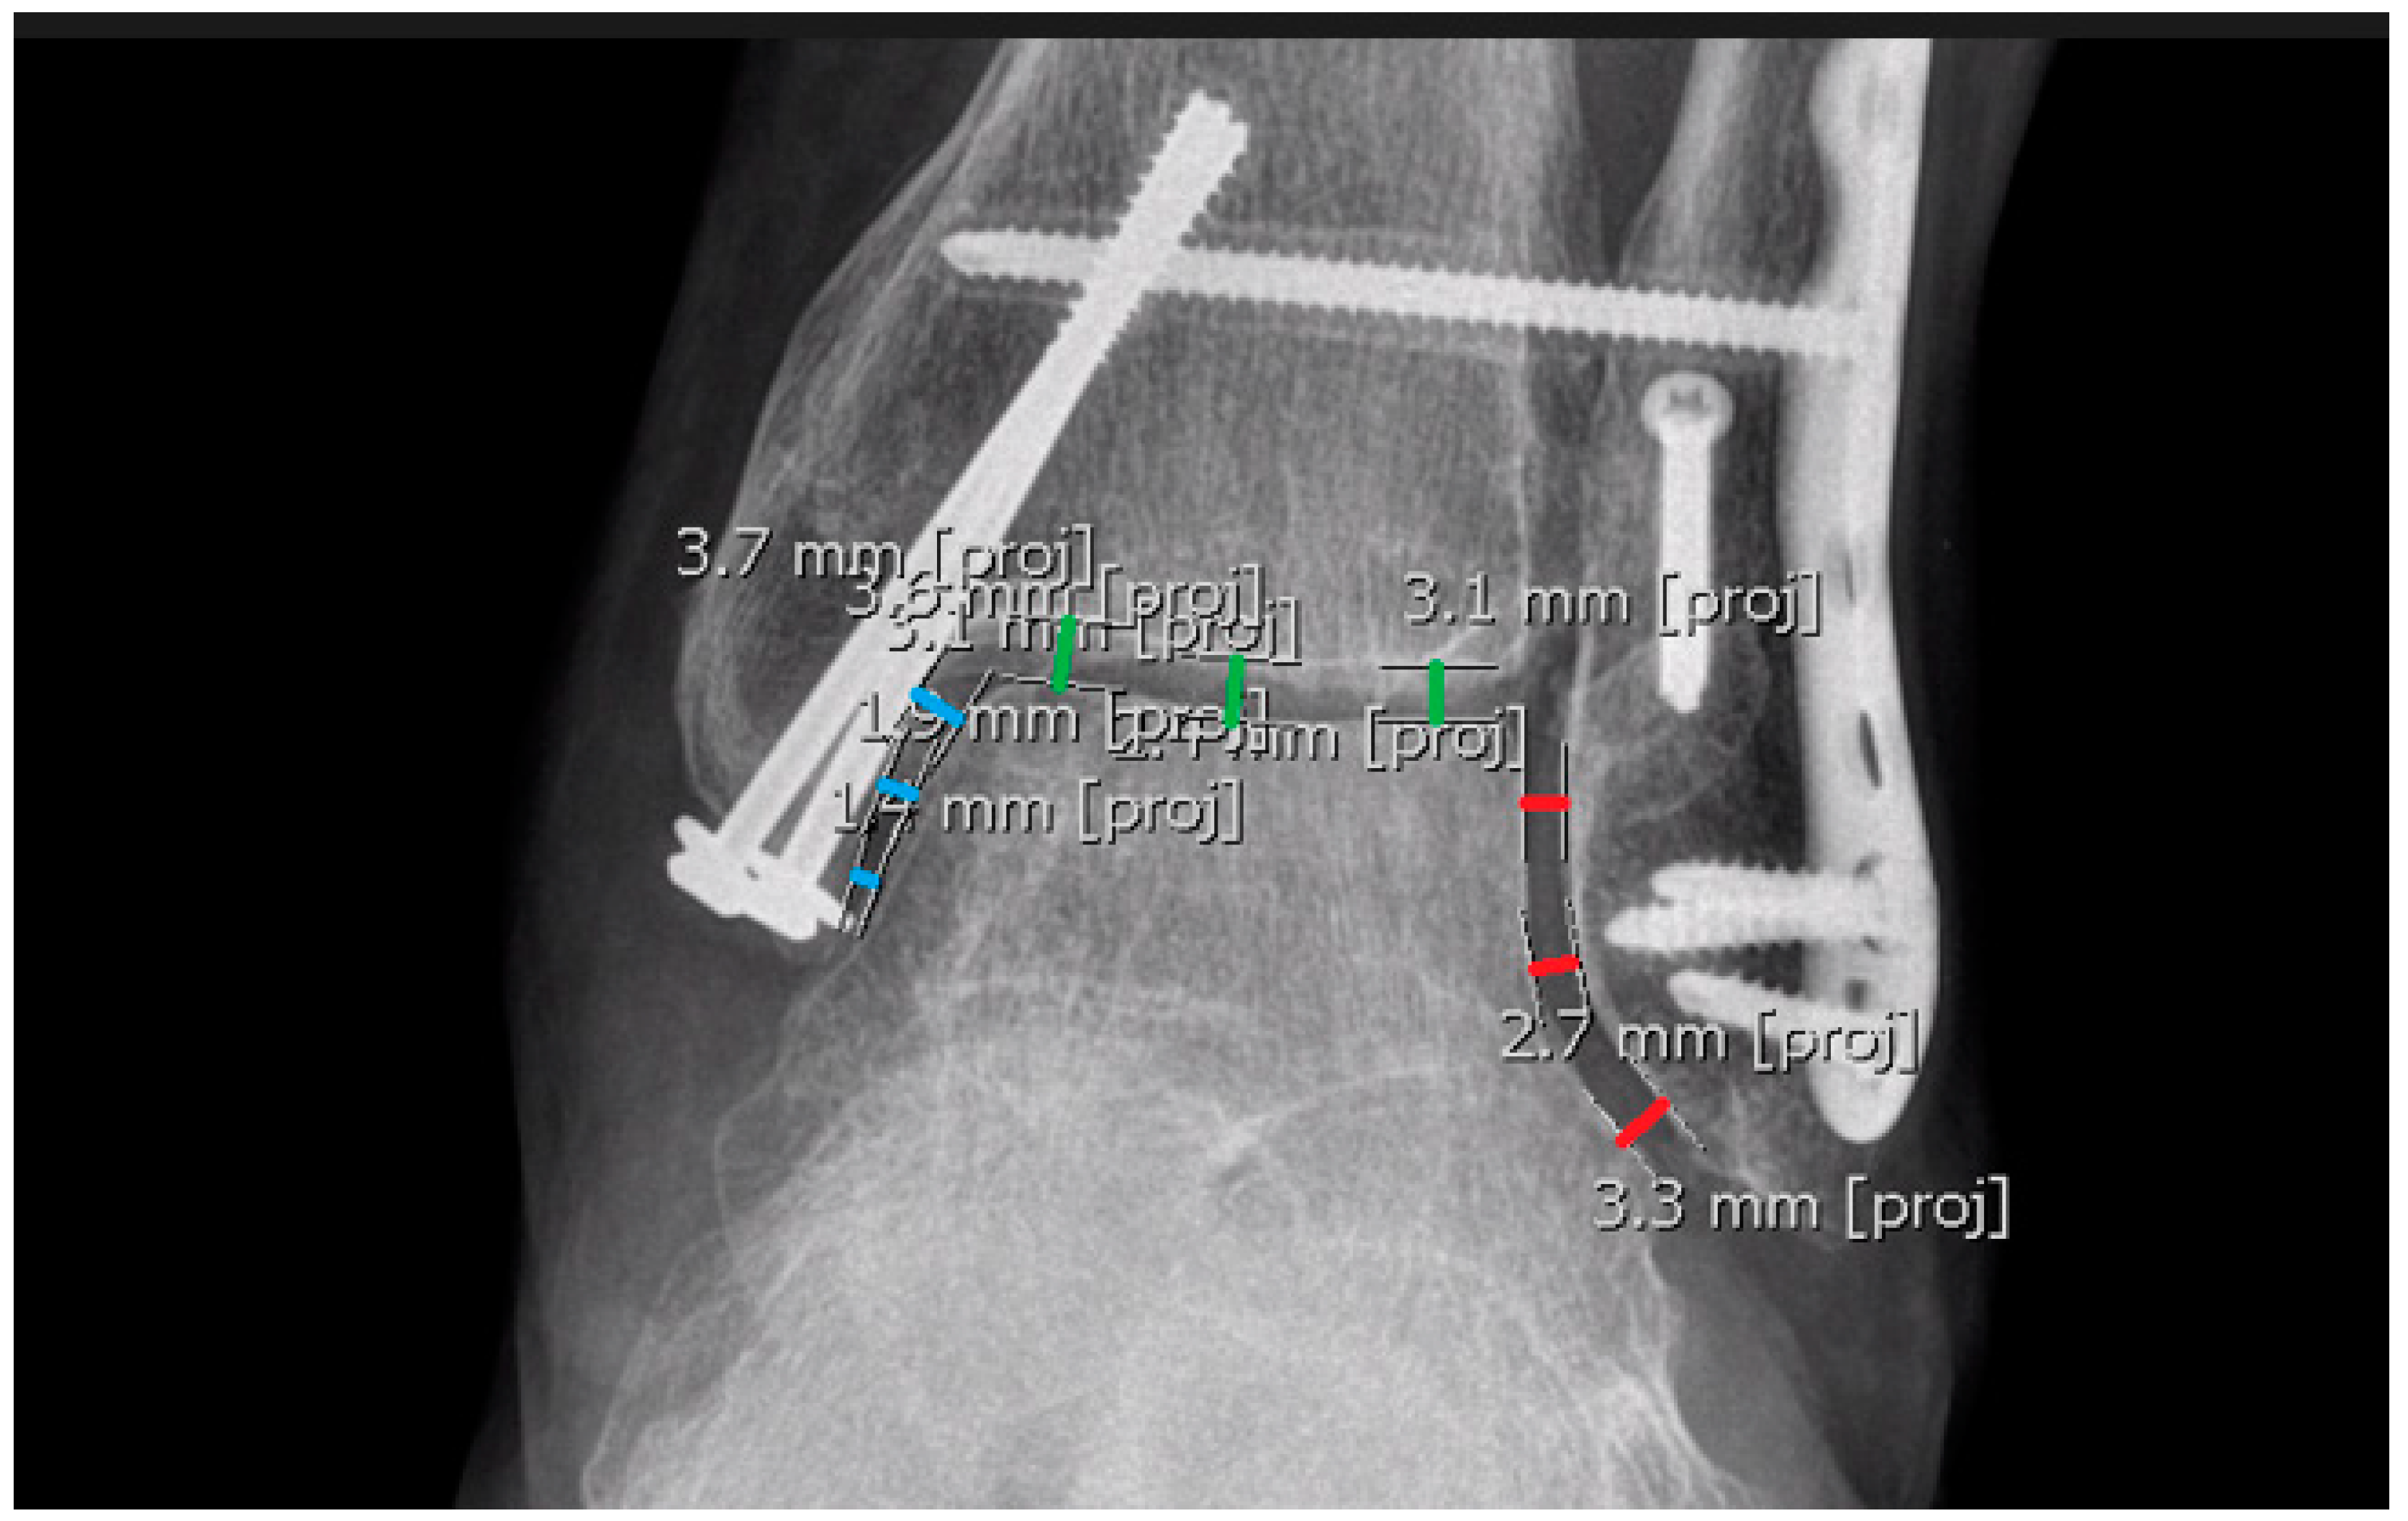

Fibular overlap—to measure the fibular overlap, we utilized 6 separate measurements (3 measurements taken twice at the widest point possible, along a line parallel to the tibial plafond) (Figure 11);

Figure 11. The red line represents the width of the fibular overlap, while the blue line indicates the plane of the tibial plafond. These lines are parallel.